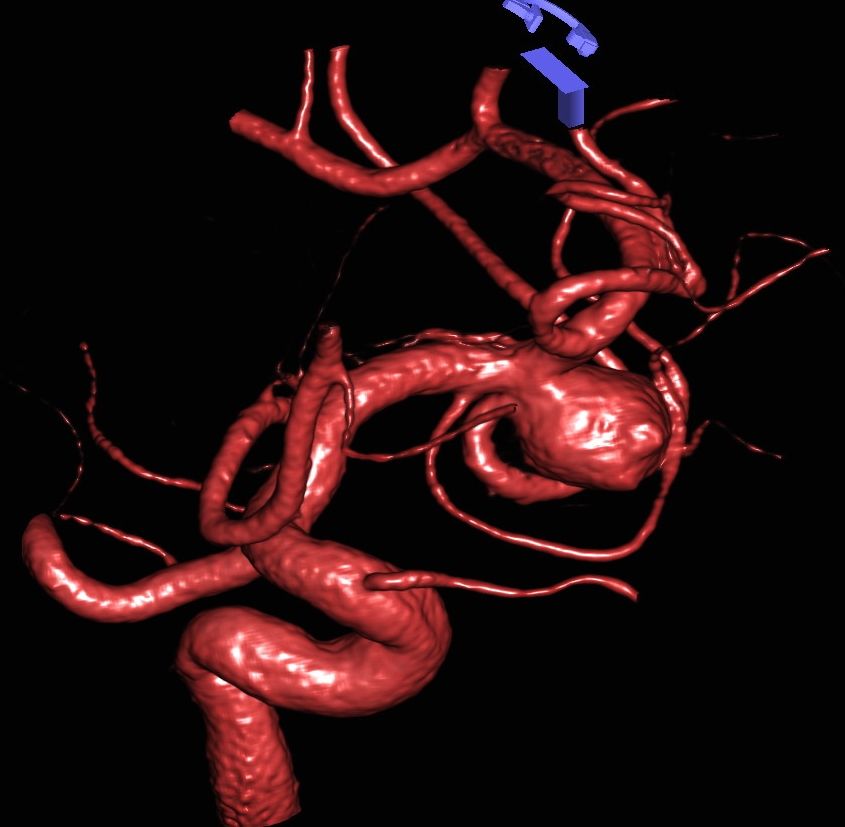

3D Darstellung eines Aneurysmas

CT-Angiographie eines gebluteten Aneurysmas

Als schnellste und sicherste Maßnahme gilt das craniale Computertomogramm (CCT). Hier lässt sich eine frische SAB meist zuverlässig darstellen, wobei auch bereits richtungsweisende Befunde, wie das Ausmaß der Blutung und eine eventuelle Lokalisation eines möglichen Aneurysmas bestimmt werden können. Darüber hinaus kann ein Angio-CCT, bei dem zusätzlich Kontrastmittel verabreicht wird und dann die intrazerebralen Blutgefäße gesondert rekonstruiert und dargestellt werden, weitere Informationen liefern. Der sogenannte “Goldstandard” zur Diagnose zerebraler Gefäßmissbildungen ist jedoch die zerebrale Angiographie. Dabei wird mit Hilfe eines speziellen Katheters über die Leisten- oder Armarterie Kontrastmittel gegeben und die zerebralen Blutgefäße hoch selektiv dargestellt. Sollten sich auf dem initialen CCT Zeichen des Hirnwasseraufstaus zeigen, der durch ein Verstopfen der Abflusskanäle durch das neu aufgetretene Blut bedingt ist, ist oft die Anlage einer Hirnwasserableitung nach außen notwendig (externe Ventrikeldrainage).